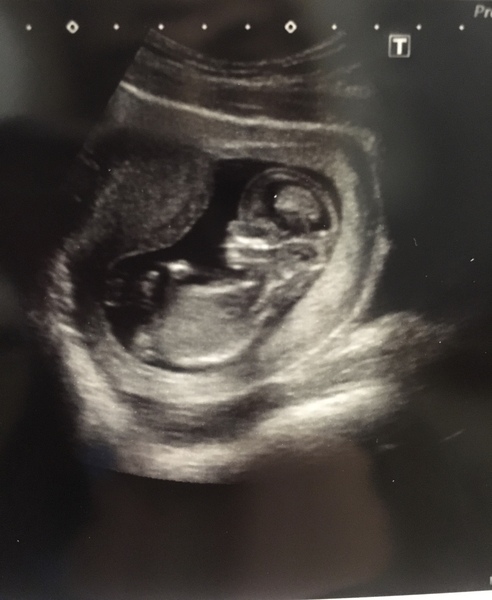

Had my scan today ladies... I'm 13 weeks exactly due 19th December

December 2018 Babies - Thread #2

@December2018 how cute!!

What a gorgeous scan @December2018 mines tomorrow and I'll be 12+5 so excited but so scared. Achy too! X

Wow @December2018 incredible pic! We're due a day apart which is exciting!

@December2018 what a perfect scan! Bub all stretched out and comfy in there!!

Congrats @December2018!!

To think.. baby is now this size.. just amazing, the mind boggles!! 😀